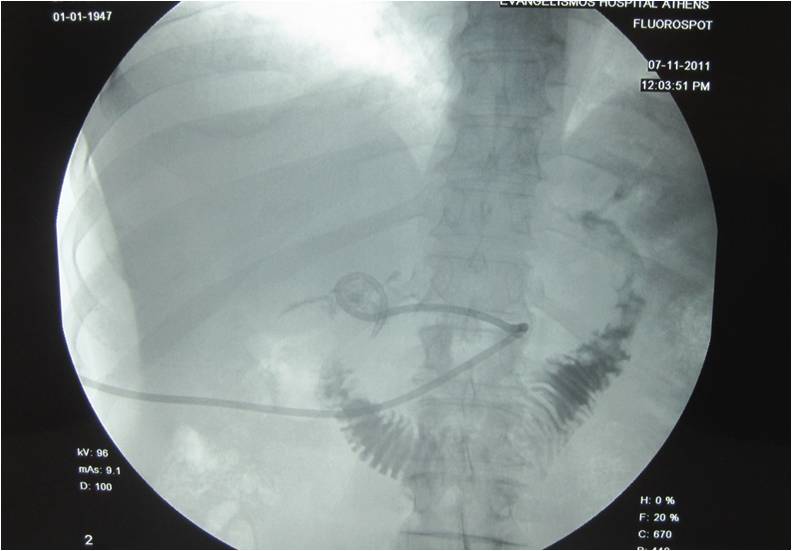

RESULTS: Eighty-nine (95.7%) patients were successfully treated. In 4 (4.3%) patients the abscesses were partially drained, patients were stabilized and subsequently treated via laparotomy. Complications included inflammation of the skin at the entry site in 4 patients, pneumothorax in 1 patient, and displacement of the catheter in 12 patients, one involving catheter migration into the duodenum. Major complications did not occur.

- Roentgenogram depicting the nephrostomy catheter in the duodenum after the infusion of contrast media through the catheter

- Catheter placement next to the duodenum for prevention of fluid collection